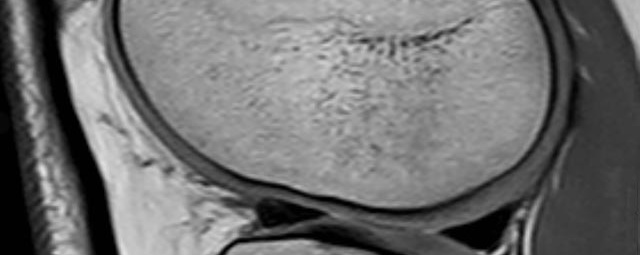

- Beurteilung von Knochen, Bändern und anderen Weichteilstrukturen der Gelenke nach Unfall.

- Arthrosediagnostik (Knorpelschaden)

- Impingement-Symptomatik

- Ursachenklärung bei wiederholter spontaner Gelenkluxation

- Ausbreitungsdiagnostik bei Gelenkentzündung, z.B. im Rahmen von rheumatischen Grunderkrankungen

- MR-Arthrographie – nach örtlicher Betäubung und gründlicher Desinfektion der Haut wird unter Lagekontrolle mit Röntgen-Durchleuchtung eine kleine Nadel in den Gelenkraum positoniert und darüber ein MR-taugliches Kontrastmittel in den Gelenkraum gespritzt. Danach wird die Nadel entfernt. Anschließend erfolgt die MRT des Gelenkes. Diese Methode stellt kleine anatomische Strukturen des Gelenkraumes verbessert dar, z.B. zur Therapieplanung vor Arthroskopie bei Sportverletzungen der Schulter oder Gelenkinstabilität.